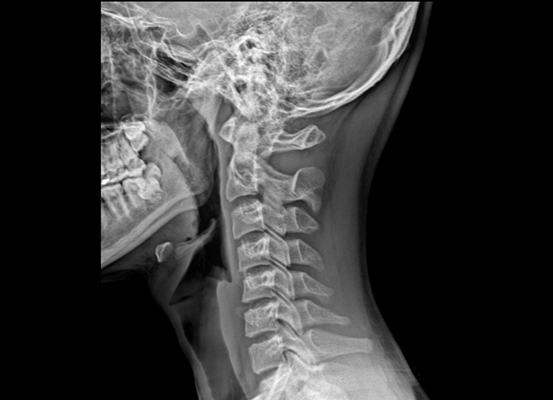

우선 목디스크란 목뼈 사이의 디스크가 깨지거나 상해 일어나는 질환을 의미합니다. 디스크는 척추뼈 사이에서 충격을 흡수하고 신경을 보호해주는 역할을 하는데, 디스크가 손상되면 신경이 압박되어 통증, 저림, 마비 등의 증상이 보여집니다.

목디스크의 증상은 여러종류가 있으며 환자마다 그 증상이 같지않게 생겨날수 있습니다. 최고 흔한 증상으로는 목의 통증입니다. 목의 통증은 목 뒤쪽, 어깨, 팔, 손까지 뻗쳐서 일어날 수 있습니다. 거기에다가, 저림, 마비, 감각 이상, 손발의 힘 저하 등의 증상이 발생할 수 있습니다.

하지만 증상이 심각하지 않은 경우라면, 보존적 치료를 통해 좋아질 수 있습니다. 보존적 치유에는 휴식, 약물치료, 물리치료, 운동치료 등이 있습니다. 그렇지만 증상이 너무 심각한 경우에는 수술이 필요할 수 있습니다.